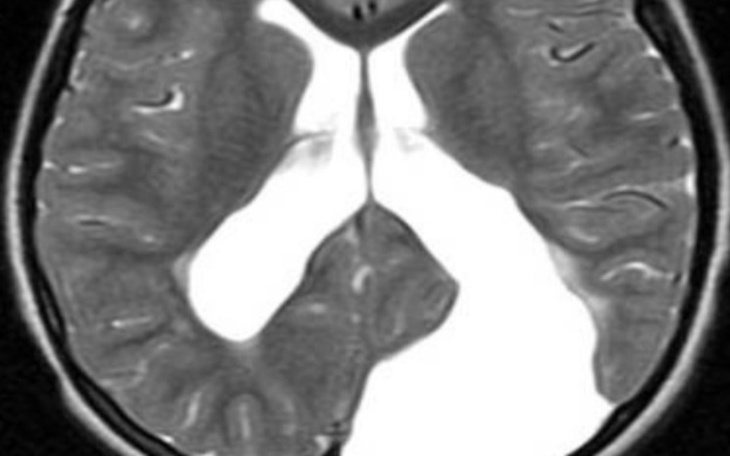

Nazywam się weronika mam 20 lat. miałam wypadek i wykryto mi ogromnego torbiela pajęczynówki w głowie.

Który ściska mi mózg zbieram na operację pomożecie